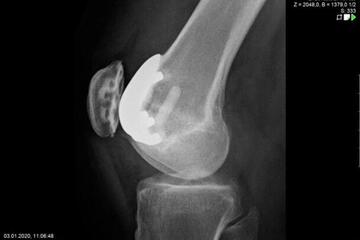

Endoprosthetics of the knee joint is an effective procedure for the treatment of symptomatic advanced wear and tear of the knee joint (gonarthrosis). If the X-ray shows a complete loss of joint space width under load, the complaints persist for more than 6 months, and the conservative therapy options have been exhausted, there is probably an indication for treatment with an artificial joint replacement (endoprosthesis). It must then be clarified which type of prosthesis is required, because today we have a large number of implants available. We distinguish between partial joints and full prostheses, and in the case of full prostheses we again distinguish between the degree of coupling of the prosthesis. If only parts of the joint are affected, only these have to be replaced and partial joints can be used. The so-called sled prostheses on the inner and outer side of the knee joint, as well as the sliding bearing replacement for problems on the kneecap, have both proven themselves effective. With full prostheses, we again differentiate between the degree of coupling of the prosthesis. Anterior and posterior cruciate ligament-supporting prostheses (surface replacement) partially coupled implants that support the inner and outer ligaments and coupled implants for complete loss of knee ligament and capsular function are used. Partially and fully coupled prostheses usually have to be inserted with stem components.

The knee prostheses are usually cemented in place, but cement-free implants are also available, which can be used, for example, in cases of cement allergies or very young patients.